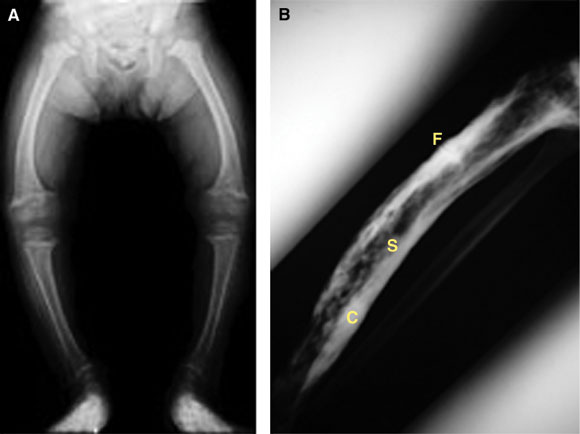

3: Anatomical abnormalities in bone disorders

A: Bowing of the tibia (genu varum) in childhood rickets, caused by poor structural integrity of osteomalacic bone.

B: Paget’s disease of the tibia, showing typical sclerotic and lytic areas (S), thickened expanded cortex (C), and a stress fracture (F). Stress fractures can be very difficult to heal and may form the site of a complete fracture.